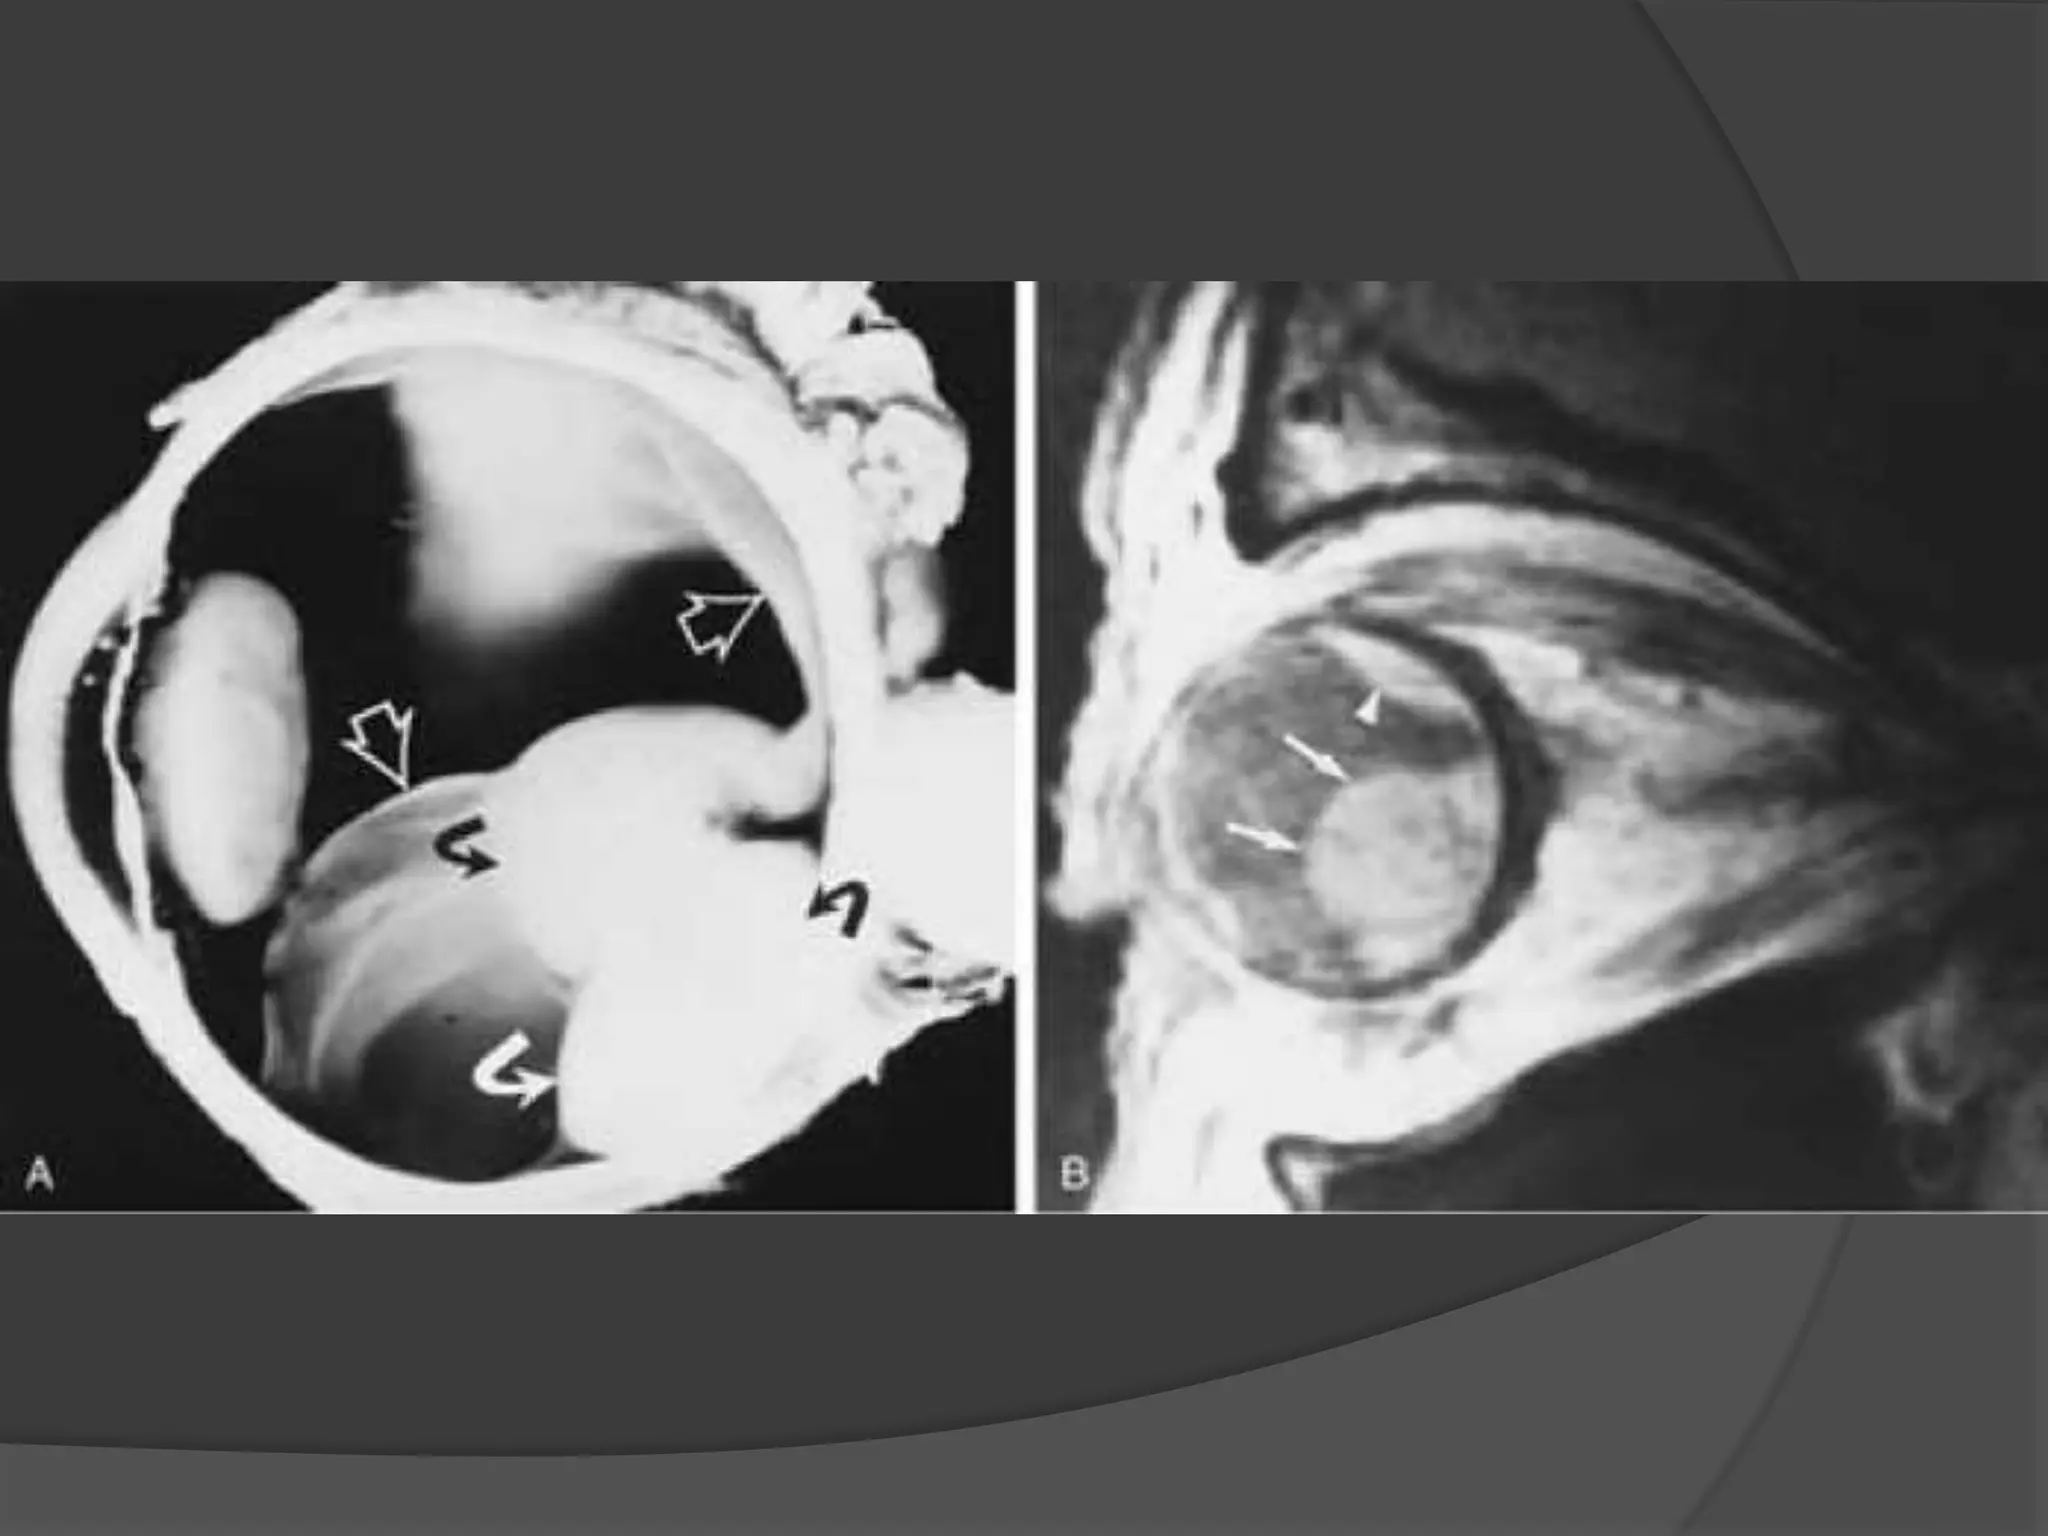

Fig A. Optic nerve Meningiomas. CT -- Enhancement of thickened right

optic nerve with elevation of optic disc (arrowhead).

Fig B. Axial T1-weighted post contrast fat-saturated image (B) demonstrates

peripheral enhancement of the thickened right optic nerve sheath.

Nonenhancing soft tissue within represents the encased optic nerve.

Fig A. Opticnerve Meningiomas. CT -- Enhancement of thickened right optic nerve with elevation of optic disc (arrowhead). Fig B. Axial T1-weighted post contrast fat-saturated image (B) demonstrates peripheral enhancement of the thickened right optic nerve sheath. Nonenhancing soft tissue within represents the encased optic nerve.